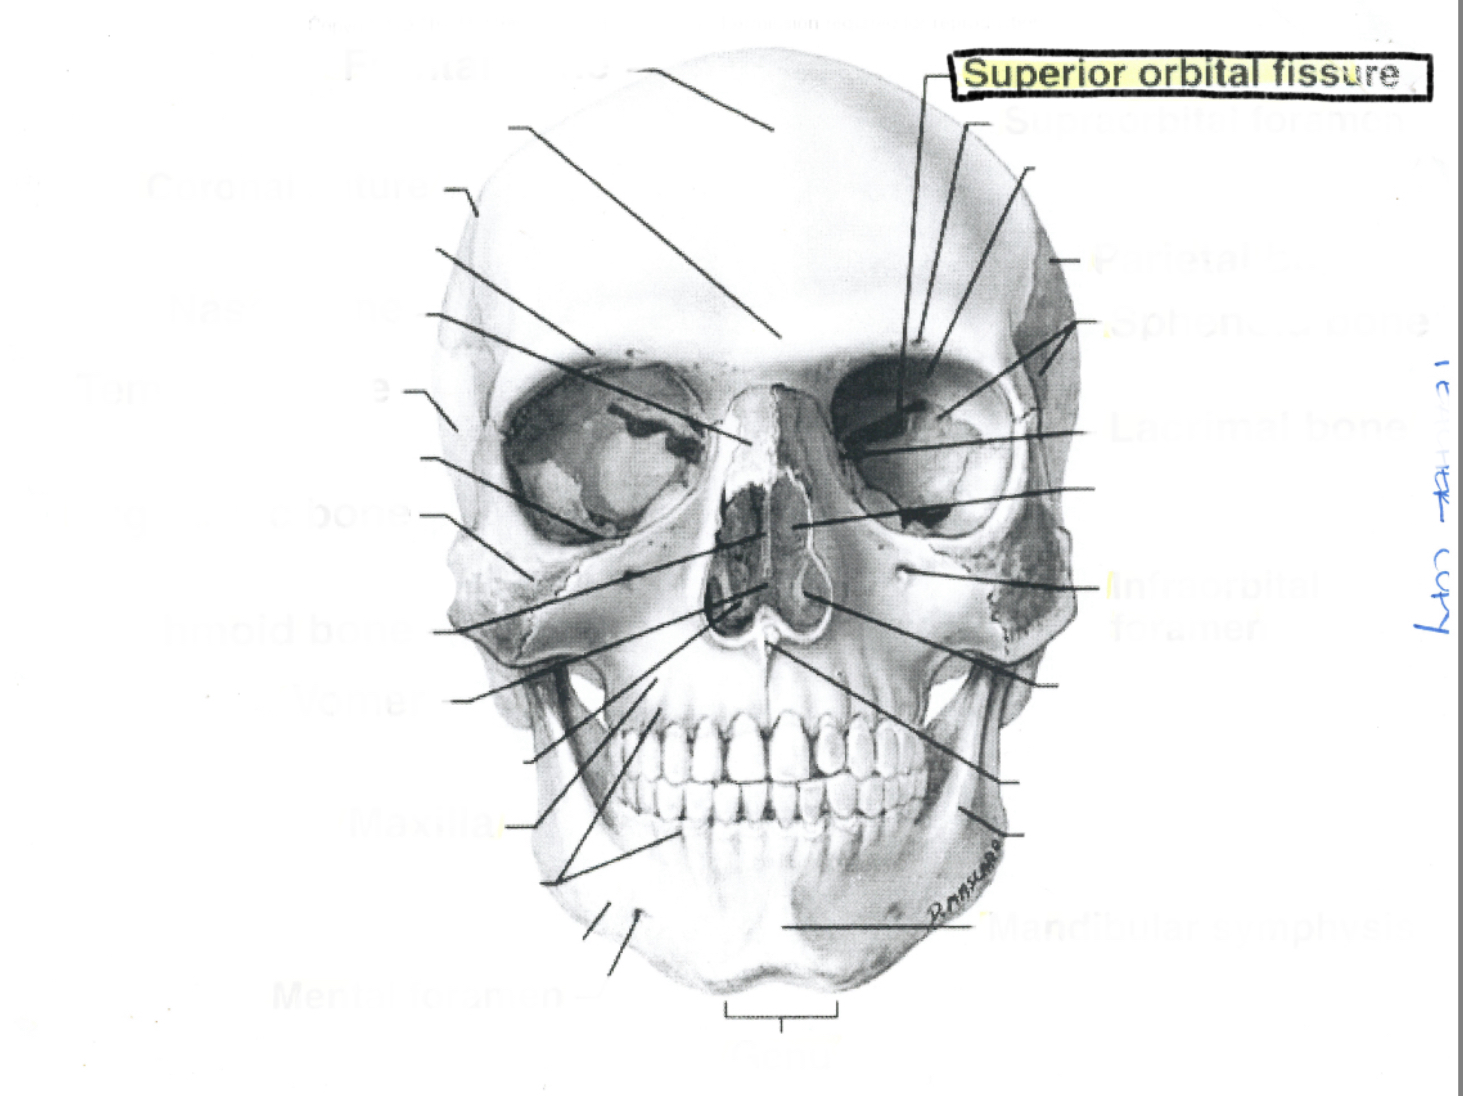

Superior orbital fissure